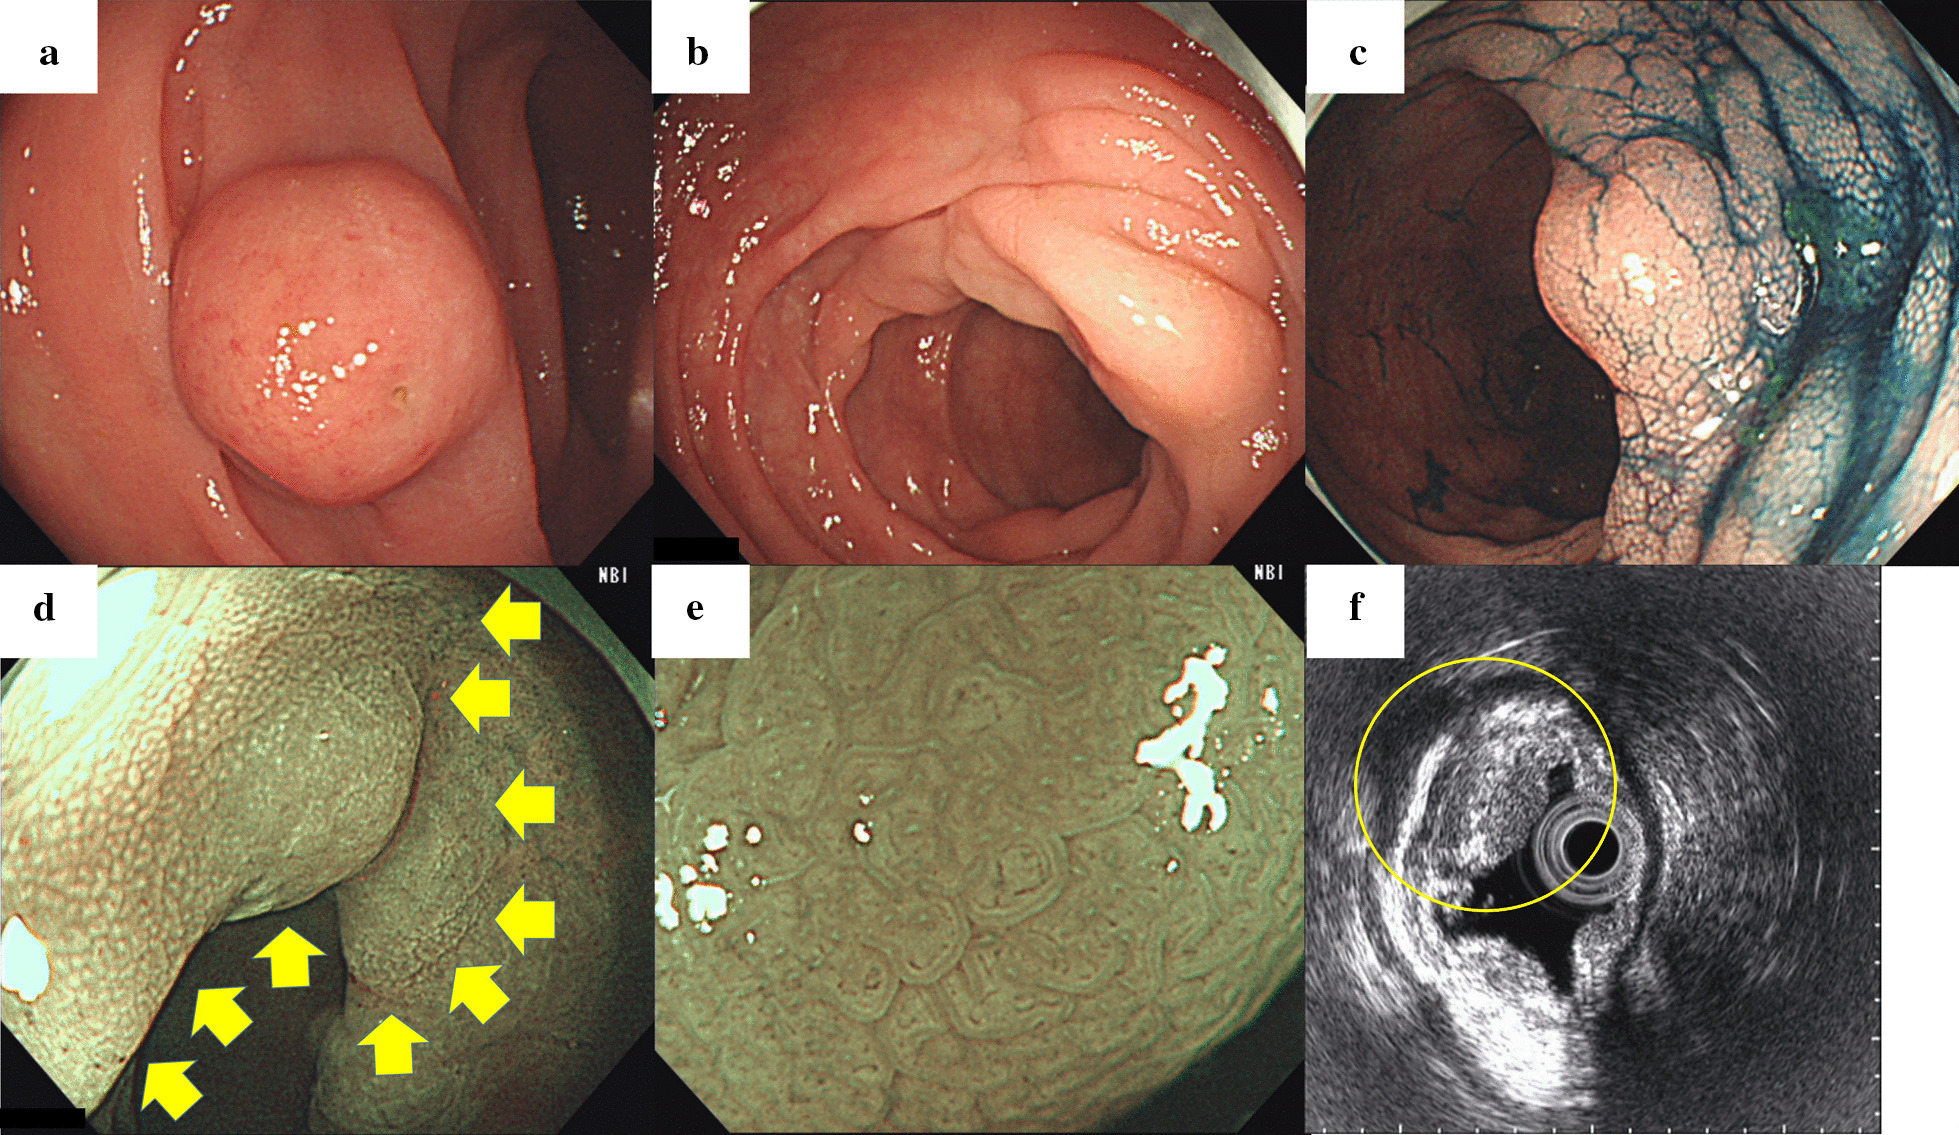

Fig. 1.

a A subepithelial lesion was observed on initial colonoscopy but subsequently disappeared. b Mucosal Schwann cell hamartomas presenting as numerous edematous elevations and submucosal tumor-like projections were observed throughout the sigmoid colon. c Indigo carmine clearly delineates a submucosal tumor-like projection. d Narrow-band imaging (NBI) of a Schwann cell hamartoma with fine white granular opacities on its surface (yellow arrows). e Magnifying narrow-band imaging revealed elongated crypt openings, increased width of intervening parts, and no visible microvessels. f Endoscopic ultrasound revealed mild, uniformly hypoechoic thickening limited to the first layer (yellow circle)

Follow-up colonoscopy conducted 2 months later revealed that the tumor had disappeared completely, leaving numerous edematous, submucosal tumor-like protrusions presenting as skip lesions throughout the sigmoid colon, over a length of 15 cm (Fig. 1b, c). Some lesions had fine white granular opacities on their surface on NBI, while others did not (Fig. 1d). All lesions displayed elongated crypt openings, increased width of intervening parts, and no visible microvessels on magnifying NBI (Fig. 1e). Endoscopic ultrasound revealed mild, homogeneously hypoechoic thickening of the first layer (superficial mucosa) with no apparent second layer (deep mucosa) involvement (Fig. 1f). Six tubular adenomas (4 in the transverse colon, 2 in the sigmoid colon), one serrated adenoma in the sigmoid colon, and four hyperplastic polyps in the sigmoid colon were resected during the same session. One of the resected hyperplastic polyps in the sigmoid colon was located on top of one of the elevated lesions with white granular opacities (Fig. 2a, b). Computed tomography with contrast was unremarkable, confirming no clear tumor or thickening of the colonic wall.

Details on endoscopic MSCH findings in the literature are scarce [8]. Elongated crypt openings, increased width of intervening parts, and no visible microvessels on magnifying NBI with or without white granular opacities were consistently observed in the multiple lesions of our case and may assist in the differential diagnosis during colonoscopy. Lesions were limited to the first layer on endoscopic ultrasound, which can clearly differentiate MSCH from submucosal tumors. This is also consistent with MSCH being localized in the lamina propria on histology. In cases where MSCH mimics submucosal tumors, this finding may help prevent unnecessary endoscopic or surgical resection.